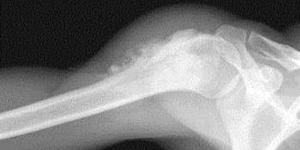

Остеогенная саркома является более нередко встречающейся и может развиться во всяком возрасте, но около 65% случаев припадают на возраст от 10 до 30 лет. Этот вид рака кости нередко встречается у деток и подростков, потому что она поражает сначала костную ткань, которая находится в стадии активного роста. Чаще всего эта саркома начинает формироваться в период величайшего роста костной ткани, а конкретно в конце созревания.Клетки остеогенной саркомы, произрастая из костной ткани, продуцируют эту ткань. Эта опухоль относится к первичным опухолям кости. Остеогенная саркома предпочтительно поражает трубчатые кости, при этом более нередко наблюдается поражение нижних(развитие опухоли с данной локализацией занимает 1-ое место)и верхних конечностей(2-ое место по частоте локализации).К раскаянию, начало болезни удается найти достаточно изредка. Наиболее нередко больного начинают тревожить боли в трубчатых костях, которые возникают фактически с момента начала роста опухоли. Обычно боли носят тупой ноющий нрав. Быстрое появление недомогай обуславливается быстротой роста опухоли и давлением ее на надкостницу и окружающие ткани. Боль при остеогенной саркоме не утихает в период покоя, в отличие от недомогай при воспалительных заболеваниях, также усиливается в ночное время и облегчение не наступает при фиксации конечности.Опухоль различается прытким ростом и ранешным метастазированием в соседние ткани и органы. Боли усиливаются по мере роста и расширения границ опухоли. В месте локализации опухоли возникает отчетливое утолщение, становится превосходно видна сосудистая сетка и возникает выраженная пастозность близких тканей.Обычно в этот период возникает контрактура сустава и хромота, ежели опухоль размещена на нижних конечностях, также резкая боль при пальпации. Прием аспирина не купирует болевой симптом. Опухоль живо произрастает в соседние ткани, наполняет мозговой канал, поражает близкие мышечные ткани. Также отличительным признаком остеогенной саркомы является раннее и обширное гематогенное метастазирование, с более нередкой локализацией в мозге и легочной ткани, при этом появление метастазов в костной ткани наблюдается очень изредка.Диагностика остеогенной саркомы не затруднена, болезнь просто выявить при поддержки рентгенографии. Если ранее остеогенная саркома с фуррором лечилась лишь при поддержки радикального способа - ампутации конечности, то современная медицина дозволяет врачевать это болезнь с постоянным сохранением всех функций кости.